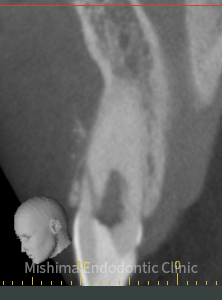

術前・術後(歯根端切除術 3ヶ月後)

| 治療内容 | 6年前にサバイバルゲームでBB弾が歯に当たり、歯が欠けた。 歯髄診査では、11,21ともにEPT+、Cold+。11は侵襲性歯頚部吸収、21は内部の炎症性吸収と診断。また、11にはパーフォレーションも認めた。 21は根管治療、ダイレクトボンディングにて対応。 11は、歯冠部の審美に対してはダイレクトボンディングにて対応。 まず侵襲性歯頚部吸収による吸収部を粘膜剥離しバイオデンティンにて外部より封鎖。後日、パーフォレーション部をバイオデンティンにて根管内部よりリペア。歯髄は正常と診断したが、予防的に根管治療を行うこととした。歯冠部からのアクセスが困難だったため、逆根管治療(歯根端切除術)にて対応。 |